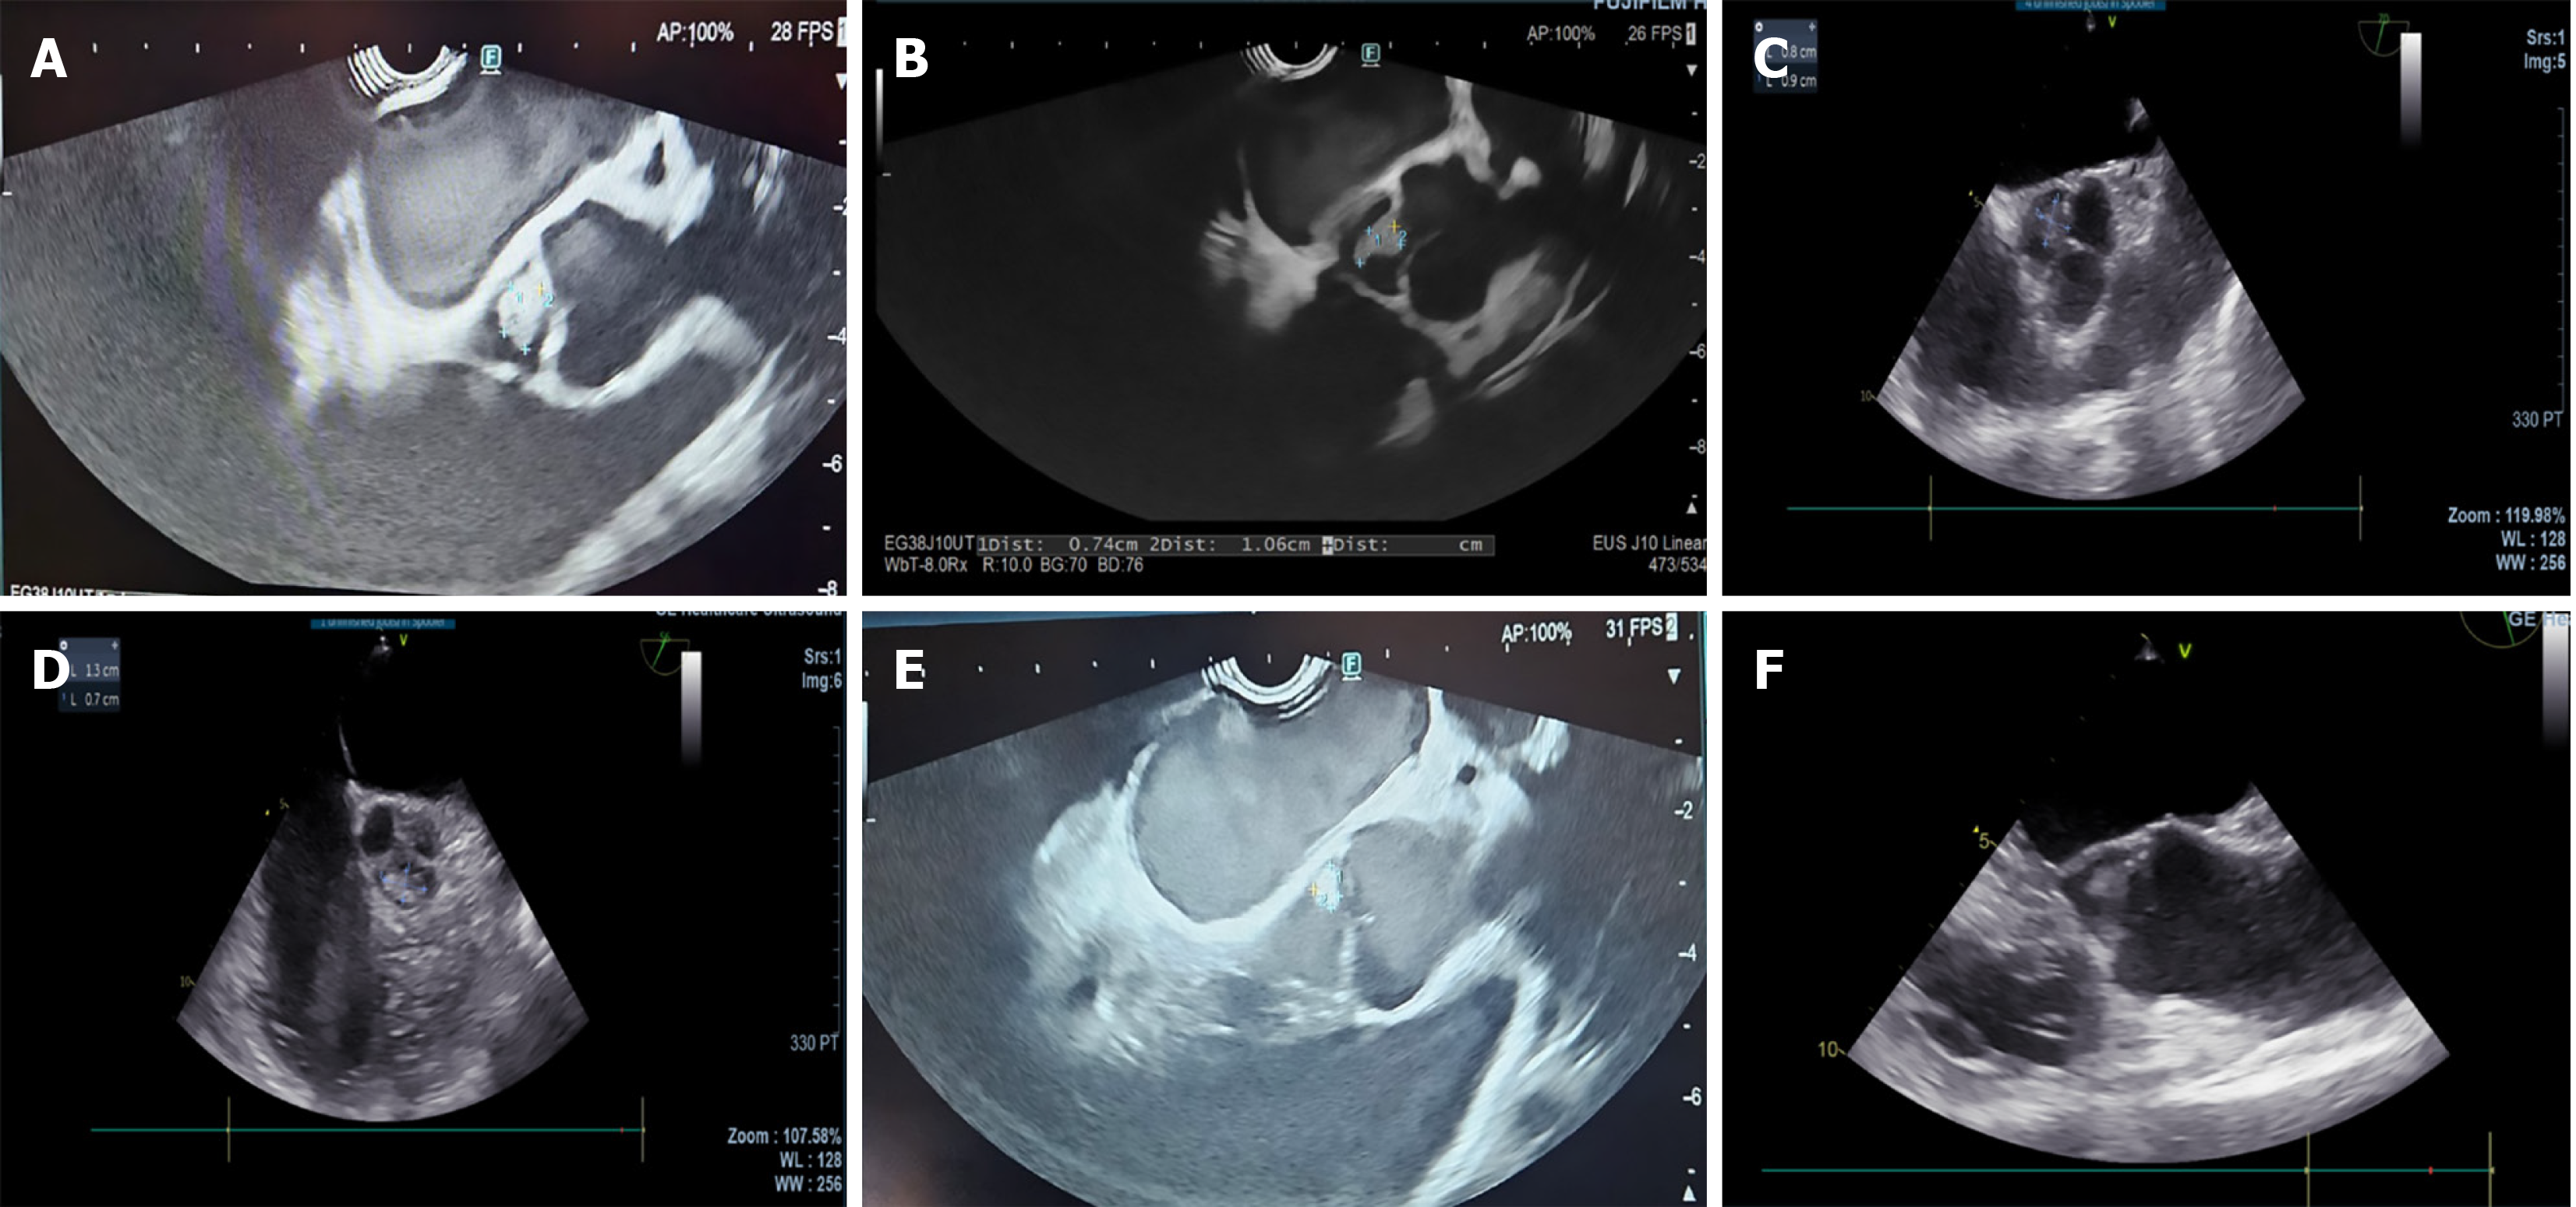

Case 1: 72-year-old female with recurrent bilateral breast cancer presented with epigastric pain, bloating, and nausea. Computed tomography (CT) revealed a suspicious lesion in the pancreatic head causing biliary and pancreatic duct obstruction. EUS and endoscopic retrograde cholangiopancreatography confirmed a poorly differentiated adenocarcinoma, staged as T3N0M0 or T2N0Mx. EUS also identified a 1 cm lesion on the non-coronary cusp of the aortic valve leaflet, suggestive of benign fibroelastoma (Figure 1A).

Case 2: 51-year-old female with Sjogren syndrome presented with hemoptysis and left iliac fossa pain. CT showed an enlarged pancreas. EUS revealed features consistent with autoimmune pancreatitis and a 1.6 cm aortic valve lesion (Figure 1B), suggestive of benign fibroelastoma, confirmed by TOE (Figure 1C).

Case 3: 42-year-old female diagnosed with obstructive choledocholithiasis underwent emergency endoscopic retrograde cholangiopancreatography in October 2024. Post-cholecystectomy complications led to infection of the gallbladder bed. EUS revealed a semi-organized collection and a 0.61 cm × 0.43 cm aortic valve lesion suggestive of fibroelastoma.

Case 1: An initial CT scan revealed a suspicious lesion in the pancreatic head, causing biliary and pancreatic duct obstructions. Staging CT confirmed a T3N0M0 pancreatic tumor. EUS staged the tumor as T2N0Mx and detected a 1 cm lesion on the non-coronary cusp of the aortic valve, suggestive of a fibroelastoma. TOE confirmed EUS findings of aortic valve lesions (Figure 1D).

Case 2: CT showed an enlarged pancreas with a normal pancreatic duct caliber and no evident soft tissue or cystic lesions. EUS revealed features consistent with autoimmune pancreatitis and incidentally identified a 1.6 cm aortic valve lesion suggestive of fibroelastoma. TOE confirmed features consistent with papillary fibroelastoma (Figure 1E).

Case 3: EUS was performed to evaluate post-cholecystectomy collection in the gallbladder bed. EUS identified a 0.61 cm × 0.43 cm lesion on the aortic valve, with characteristics suggestive of a fibroelastoma (Figure 1F).